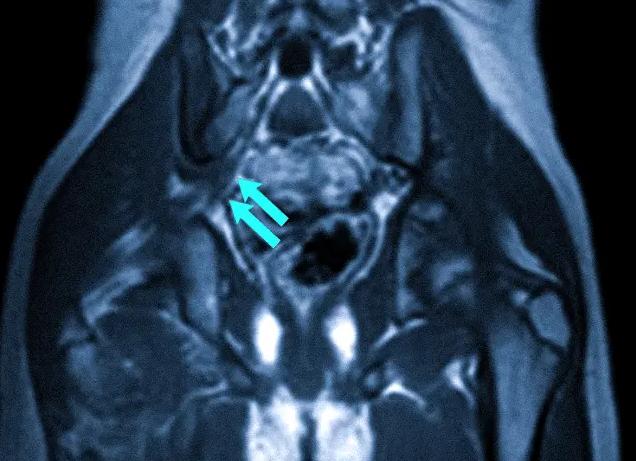

Визуализировать органы шеи и мягкие ткани очень сложно на рентгене, для этого применяются контрасты, да и то диагноз выставляют косвенно. Революционным открытием в этом направлении стало МРТ (магнитно-резонансная томография), она позволяет увидеть патологию мягких тканей. У человека в области шеи, головы есть много органов, сосудов, нервов, которые необходимо визуализировать, чтобы установить точный диагноз. Проведенное МРТ шейного отдела, головы позволяет это сделать наиболее качественно и оптимально.